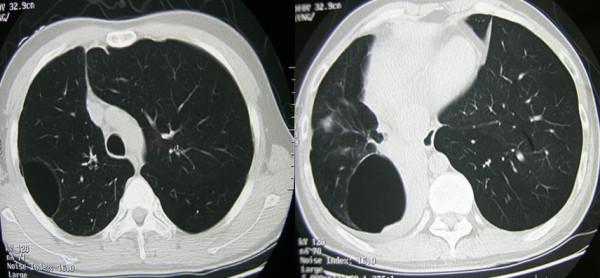

A 31-year-old asthmatic Chinese man presented with recurrent spontaneous pneumothorax and underwent lobectomy due to persistent air leakage. Aspergillus was detected histopathologically in the visceral pleural cavity. He was treated with itraconazole at 200 mg a day, and nine months later he had no recurrent pneumothorax or aspergillus infection.

一名31岁的中国哮喘男性患者出现复发性自发性气胸,因持续漏气接受了肺叶切除术。在内脏胸膜腔中通过组织病理学检测到曲霉菌。他接受了每日200毫克的伊曲康唑治疗,九个月后未再出现复发性气胸或曲霉菌感染。